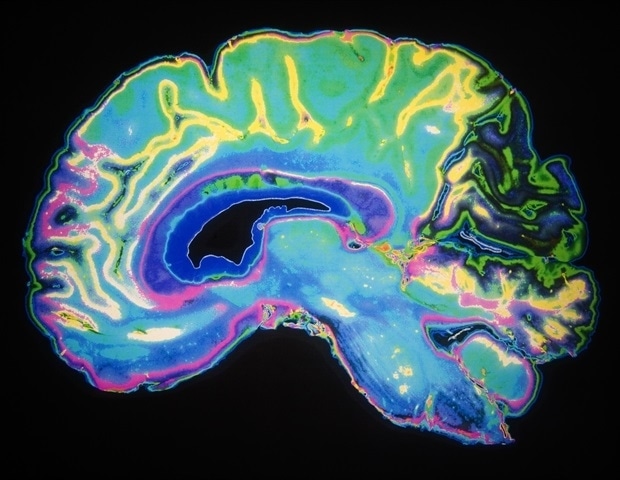

Groundbreaking research from the Technical University of Munich (TUM) and the Friedrich-Alexander-University Erlangen-Nuremberg (FAU) reveals that functional MRI (fMRI) signals may not accurately represent true brain activity. The study indicates that in approximately 40 percent of cases, higher fMRI signals correspond to reduced brain activity, challenging long-standing assumptions about the relationship between blood flow and neuronal activity.

During these tasks, the team, led by Dr. Samira Epp and PD Dr. Valentin Riedl, now a professor at FAU, employed a novel quantitative MRI technique to measure actual oxygen consumption in real time. Their results demonstrated that in certain brain regions, increased oxygen consumption did not align with expected increases in blood flow. Instead, the analysis revealed that these areas were optimizing oxygen extraction from the existing blood supply, meeting their energy demands more efficiently without necessitating greater perfusion.